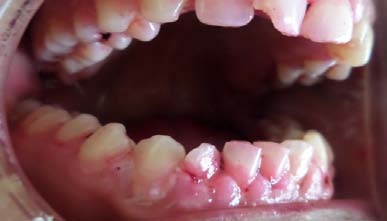

A 20 year-old male patient sought to a private practice with a chief complaint for discoloration and dull pain in maxillary anterior teeth region since 1 year. Clinical examination reveals non vital response of 11, 21. Radio graphically, maxillary left central incisor showed the radiolucency in the middle third of the root surface indicating of internal resoprtion (figure 1). The patient reports he did not remember trauma history in the same region. It was decided to complete the endodontic therapy for 11, 21.